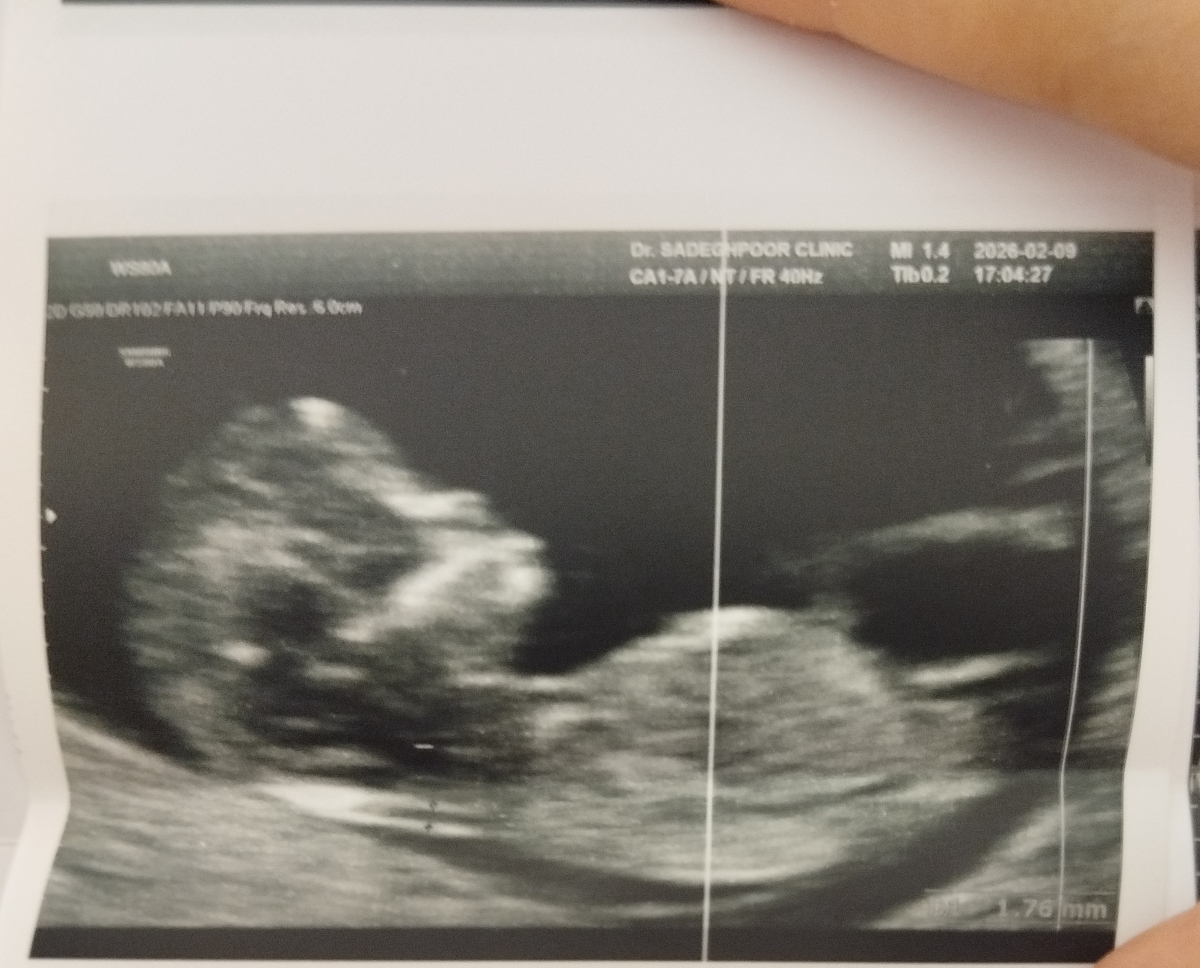

خانوما دیدم همه عکس انتیشون رو گذاشتن، دلم خواست منم بذارم.

حدس میزنین نینی چی باشه؟ 🥲😍

تشخیص جنسیت 😬 😀

طبق نظر دکترم توی دوازده هفته و یک روز رفتم

اونجا گفتن دوازده هفته و سه روزته